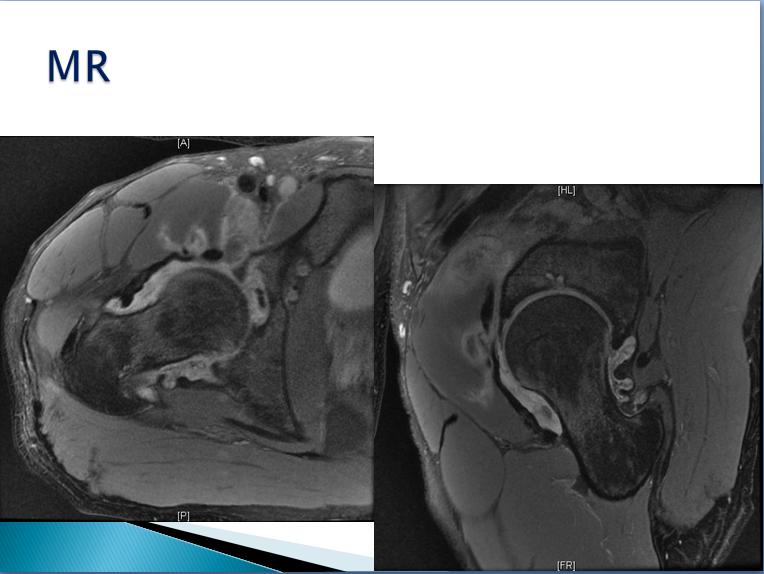

第三届中国超声造影大会病例大赛北医三院超声科获奖病例展示(三)